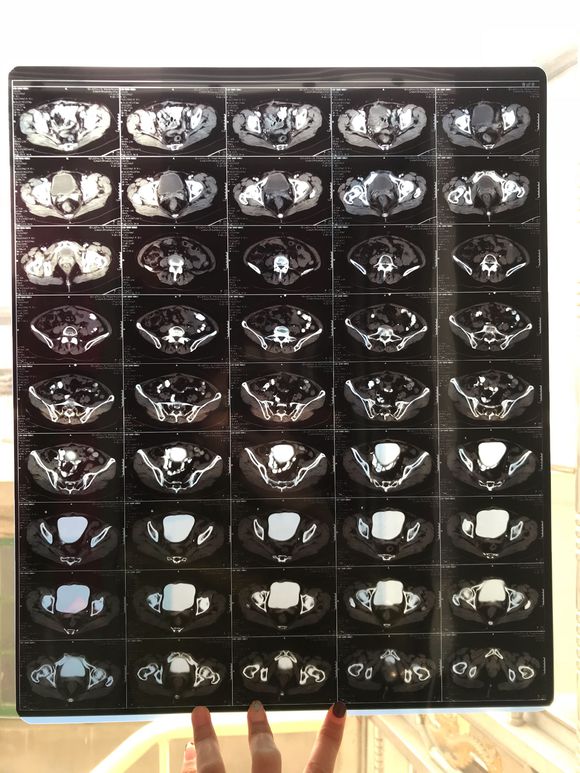

和你的故事 02019-04-09 患者家属我妈妈的病理结果报告,3期c1,大家可以帮忙看看吗,跪求了!我很急,谢谢!想知道是否严重,目前等术后出院后去肿瘤医院...

0人关注 4个回复 3469次浏览 -